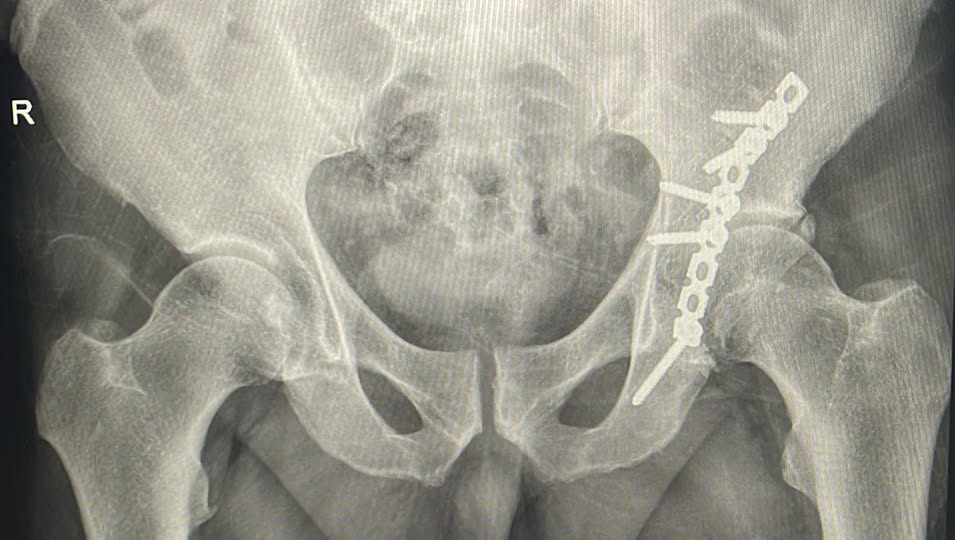

Második alkalommal végeztek sikeres műtétet a Csíkszeredai Megyei Sürgősségi Kórházban acetabulum-törés (csípőízületi vápatörés) kezelésére, közölte az intézmény.

Az acetabulum törései nagy erejű traumák, például közúti balesetek következményeként jelentkeznek. Összetett műtéti megoldást és hosszú rehabilitációs folyamatot igényelnek, hogy megelőzzék a maradandó mozgáskorlátozottságot. A műtét során a feltárás összetett és veszélyes folyamat, ami után az elmozdult csontdarabokat először visszahelyezik a normál helyzetükbe. A sebész ezután fémlemezeket és csavarokat rögzít a csont külső felületére, hogy összetartsa a tört darabokat, ameddig az meggyógyul anatómiai pozícióban. A helyes csontredukciót röntgenkészülékkel ellenőrzik.